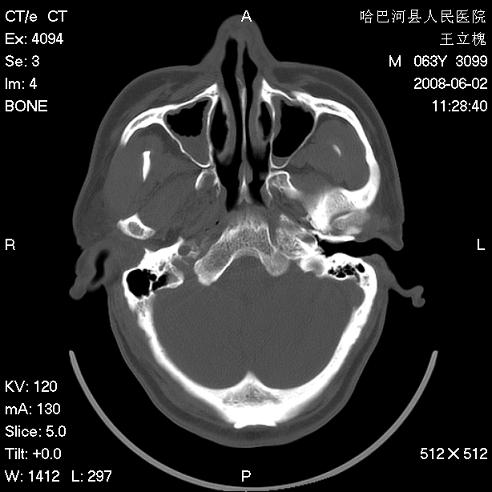

标题: CT13803:反复性鼻塞、流涕一年余 [打印本页]

标题: CT13803:反复性鼻塞、流涕一年余

副鼻窦炎,右上额窦积脓。左眼肌锥内见致密影,视神經受压

1.全组副鼻窦炎2.双侧上颌窦积液

1)全副鼻窦炎(左侧上颌窦黏膜下囊肿或息肉)。2)左眼眶肌锥内不规则小结节状软组织密度影;考虑为小血管瘤可能。建议行ct增强扫描检查。

全组副鼻窦炎,左侧肌锥内不规则形软组织肿块影,与眼外肌密度相当,左侧视神经受压,肿块与视神经及眼外肌分界清晰,眼外肌无增粗,眶壁无破坏,球后脂肪间隙不模糊,考虑良性改变,小血管瘤或神经源性肿瘤可能,建议增强扫描。

谢谢,增强扫描做了,眶内病灶与海绵窦同步明显强化,血管瘤